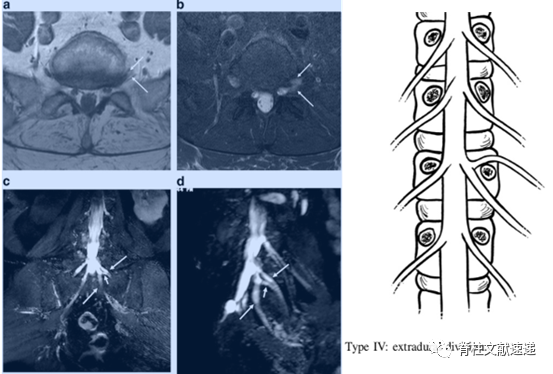

2.MR神经成像(MR neurography imaging)能够更清楚的显示异常神经根。

上图MR神经成像(右下)显示了双侧L5和S1并根异常。属于Neidre分型I型,最常见类型。

上图MR神经成像显示了左侧L5和S1并根异常。属于Kadish分型IV型或者Neidre分型II型,在L5/S1左侧椎间孔内有2根神经根穿出。

MR神经成像与术中对照。异常神经根为Neidre分型IA型,从上位神经根发出,然后与硬膜平行向下走形,从下一个椎弓根下穿出。